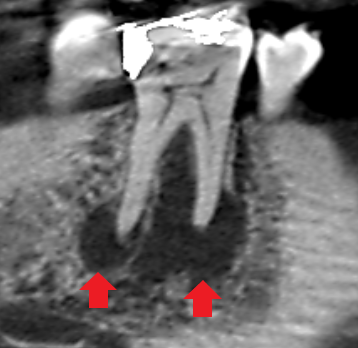

実際に「根管」の画像をご覧頂きましょう。歯の中にある黒い筋が根管です。